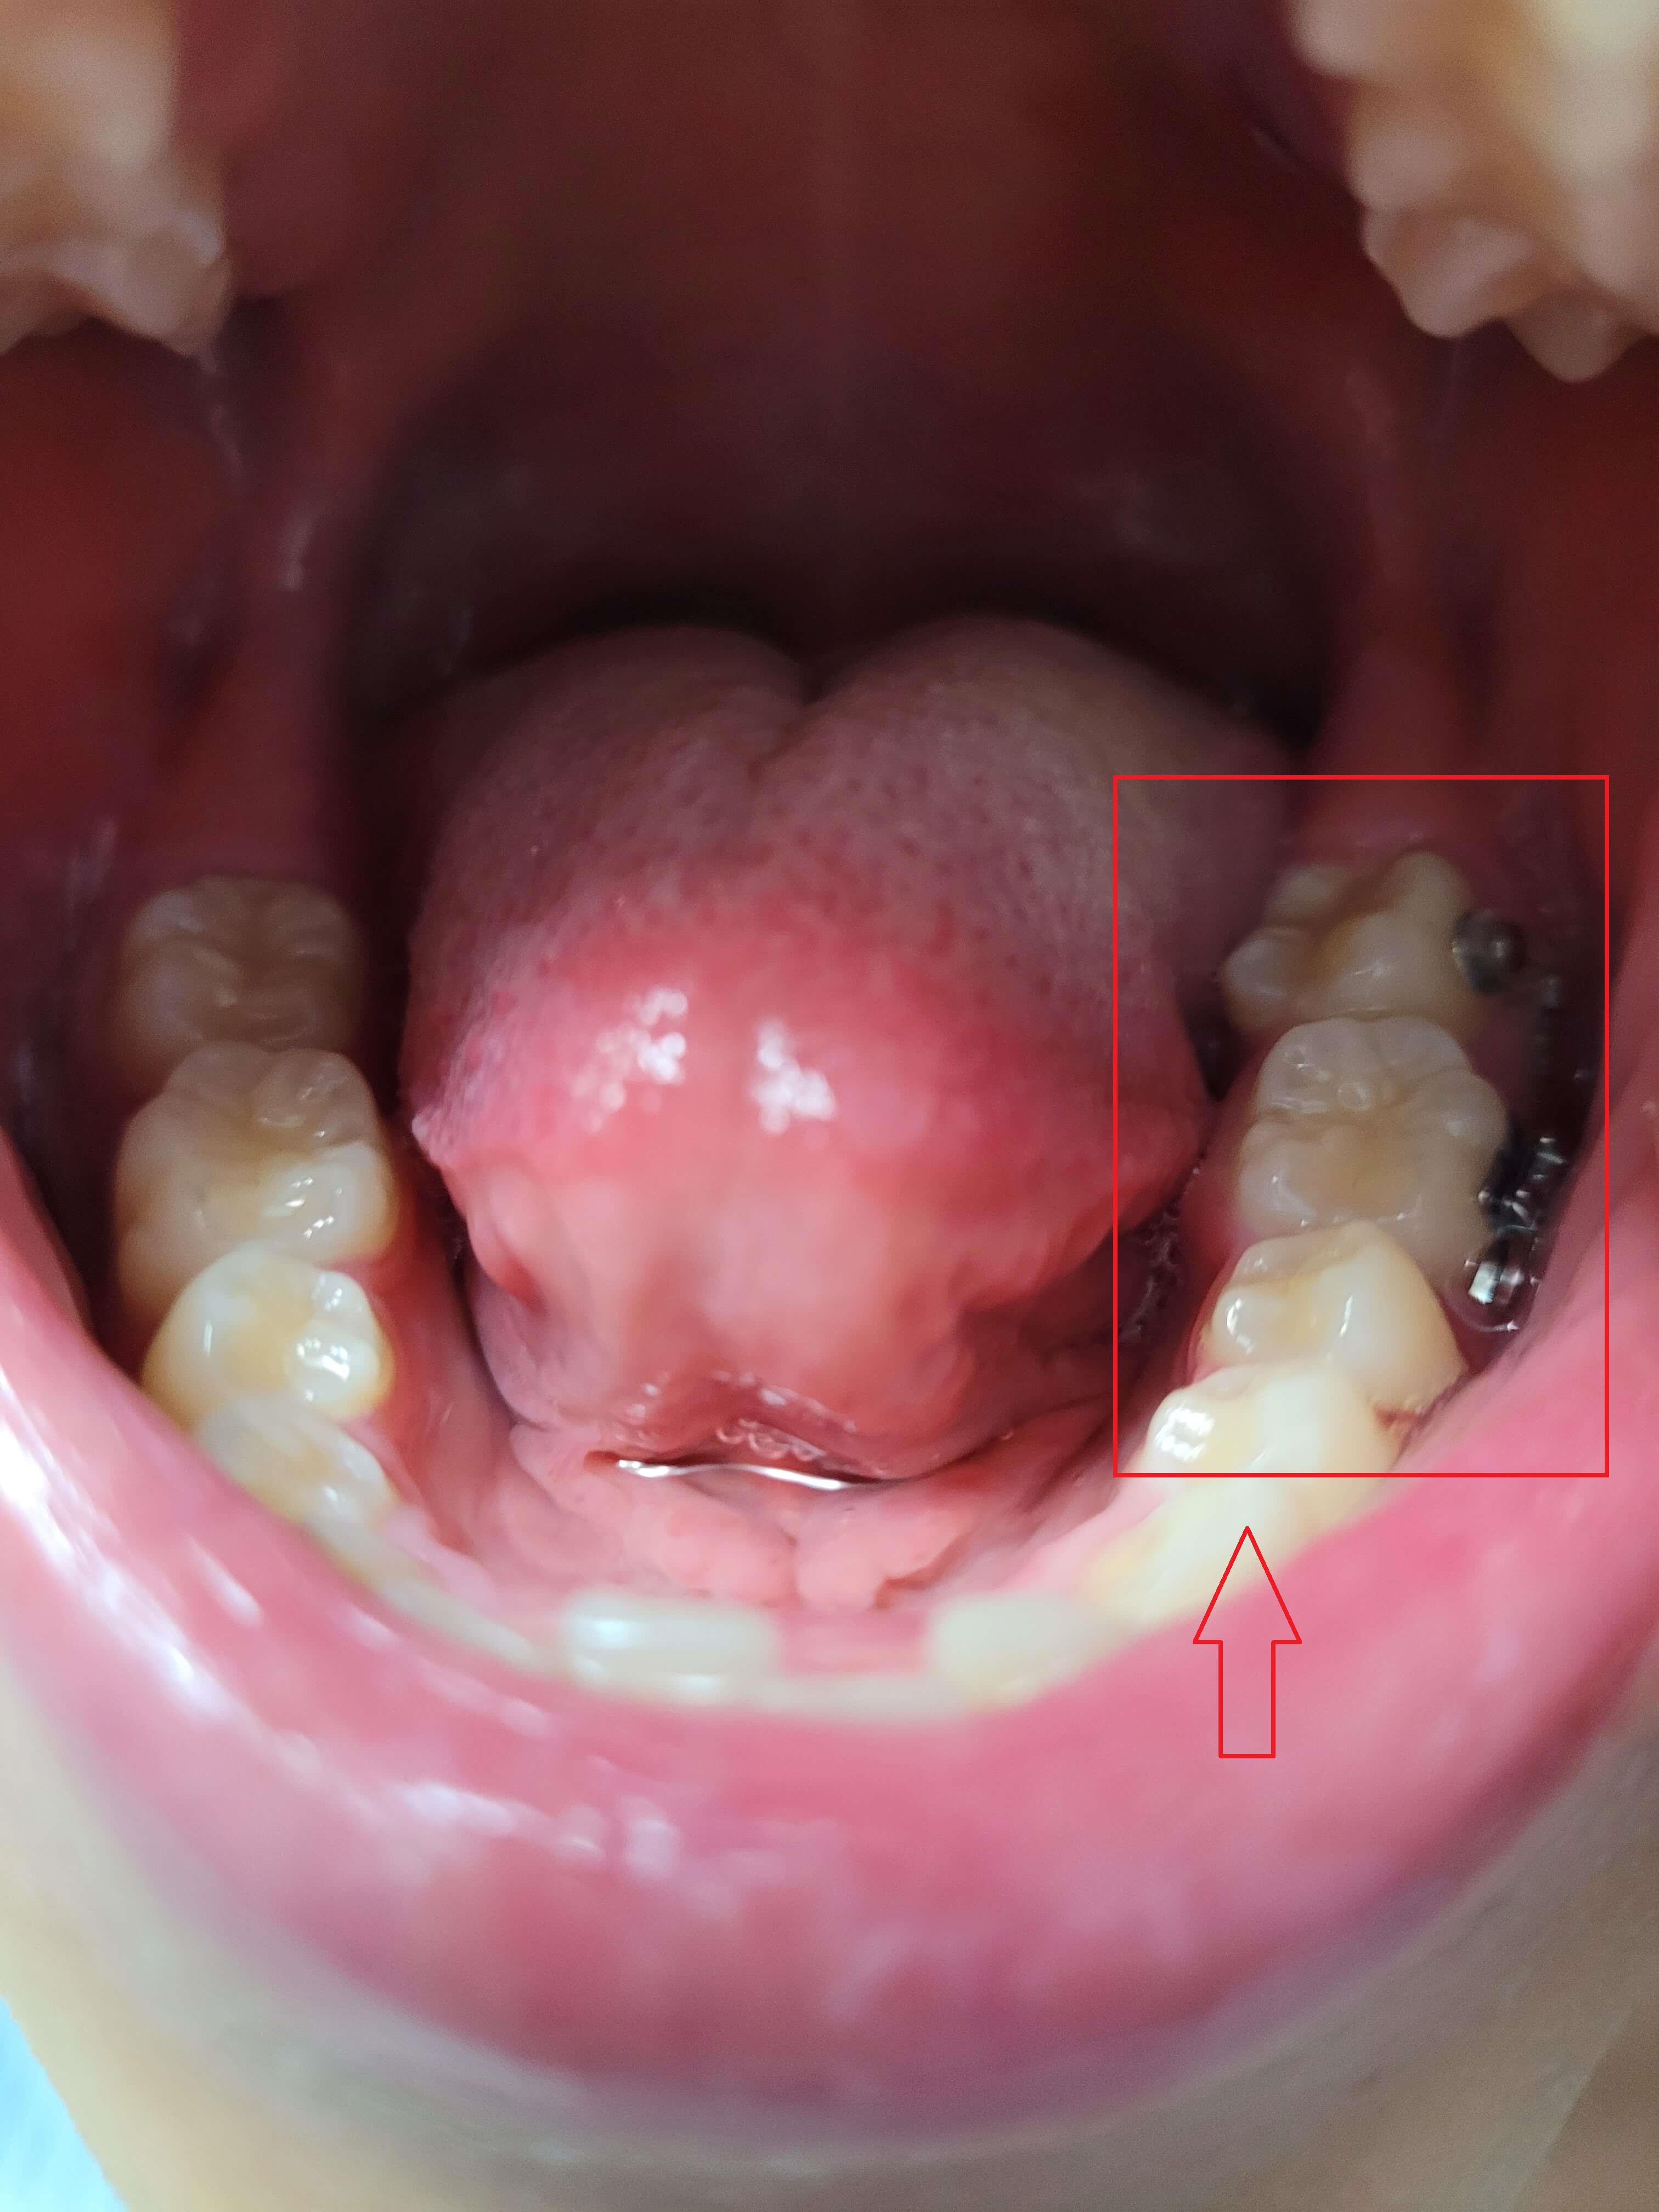

◎ 아들치아교정 전 상태확인 (과개교합사진)

- 「윗 앞니 과개교합」